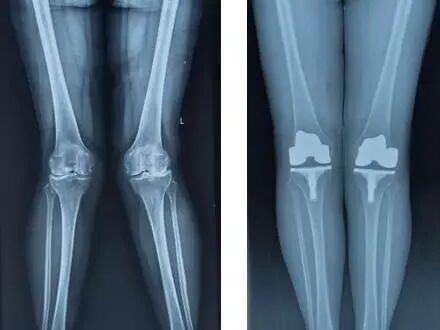

李教授引用中美关节置换(Joint Arthroplasty)数据作为报告切入,分析疾病导向的临床服务,指出老年骨科的发展应是整合骨骼肌肉退变疾患,老年骨肌退变衰老预防,内外科综合分级治疗、MDT整合医疗、快速康复、慢病管理的新领域。应设立多学科联合门诊(MDT),实现一次挂号、多科协同诊疗为方便老年患者,建设“骨质疏松专病门诊”、“风湿骨肌痛专病门诊”,覆盖筛查、预防、慢病管理、干预与系统随访等健康管理体系。

他分享了标准化运营体系助力骨科业务发展与患者满意度双提升。在东大医院骨关节科,多学科协作驱动下的"加速康复EARS"模式已应用成熟,较传统模式大幅缩短患者住院时间,他引用以案例说明,骨科、麻醉科、康复科、实现一体化协同让无陪护、早下床、早康复的关节置换手术成为科室名片,并形成品牌效应。在骨关节外科人才梯队培养方面,提出成立宏信健康关节学院、宏信健康骨科菁英团、宏信健康骨科青年医师协会,以申报评审骨科技术、宏信骨科专家课堂、Journal club、Surgery conference等形式加强学科内涵建设、提升专业水平,促进学术交流和临床实践提升。